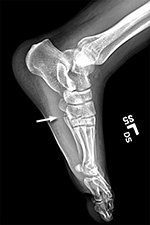

i had nothing to lose and was curious to get my hands on my broken foot x-rays from last year 2 years ago, so i went to the sub-basement of the bigelow building. i wasn't sure if i could get it today, and i wasn't sure if i had to pay. the man who helped me said he'd put everything onto a disc, and that he could do it while i waited. what i thought would be a quick wait ended up being almost 45 minutes. the big hold up were the MRI scans, which i already had a copy. was he downloading the images via 1990's modem technology? i also learned that if you request the images for personal use then you'd have to pay, but it's not seriously enforced, and if you just make up a doctor, you can get everything for free (they give you the disc anyway, they don't mail it out).